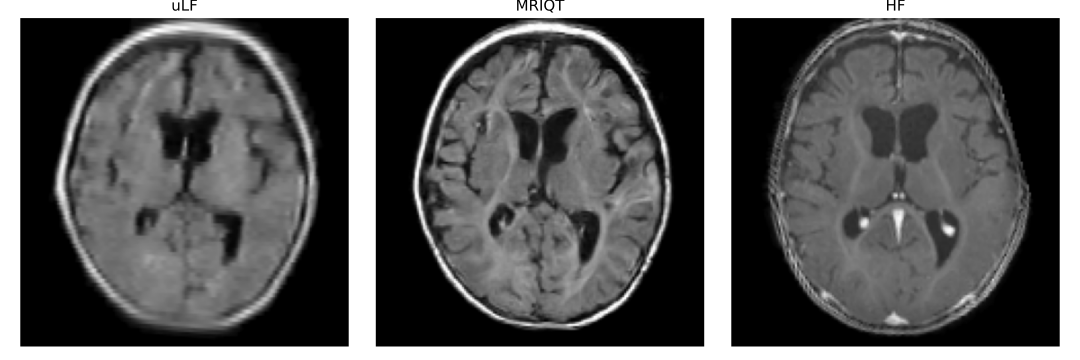

Refer to caption

Fig. 1: Our MRIQT restores fine anatomical structures and contrast in portable uLF scans, producing HF-like images.